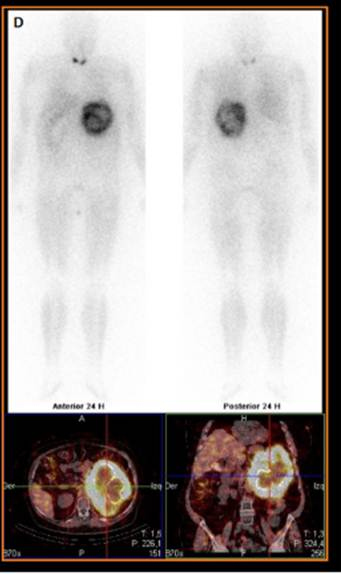

El estudio híbrido PET/CT con 18F-FDG mostró una gigantesca masa suprarrenal izquierda con incremento metabólico en su periferia (SUVmáx = 5,5) y ausencia de captación en los componentes quísticos centrales y áreas calcificadas. Dichos hallazgos eran compatibles con proceso neoformativo, cuyo grado metabólico no sugería carcinoma (fig.1C). Finalmente, la gammagrafía simpáticoadrenal con 370 MBq de 123I-MIBG y técnica híbrida SPECT/CT reveló intenso depósito focal del trazador a nivel de la glándula suprarrenal izquierda, correspondiente a un feocromocitoma con necrosis intratumoral asociada (fig. 2). Se inició bloqueo-alfa preoperatorio (fenoxibenzamina 5 mg) y se realizó suprarrenalectomía izquierda con nefrectomía ipsilateral en segundo tiempo. El estudio anatomopatológico confirmó feocromocitoma maligno con PASS-score (Pheochromocytoma of Adrenal gland Scaled-Score) de 7, potencial alto de malignidad. Actualmente la paciente se encuentra asintomática, habiendo cedido los episodios diarreicos y con normalización de cifras tensionales tras la cirugía.